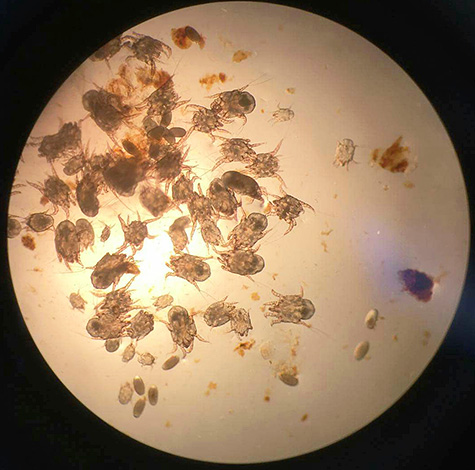

קרדית Otodect - קטנה מאוד טפיליםמגיע לאורך של 0.8 מ"מ. גופם סגלגל, מעט מוארך, בצבע צהוב או חום.

התמונה למטה מראה כיצד נראות קרדיות כאלה תחת מיקרוסקופ: